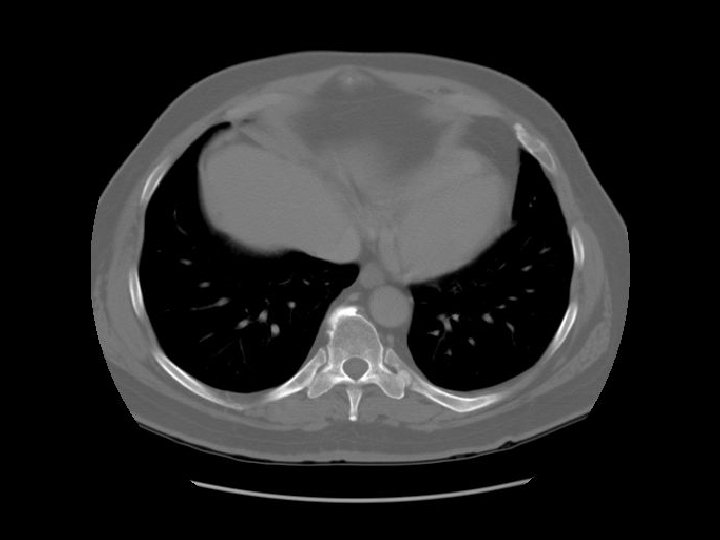

Ascending aorta Main pulmonary artery Descending aorta

Contrast in SVC is diluted by blood from the azygous vein. Esophagus Azygous vein

Left pulmonary artery Carina

Right pulmonary artery Main pulmonary artery RUL bronchus Left pulmonary artery

Left main bronchus

SVC Intermediate bronchus LUL division

Ascending aorta

Rt atrium